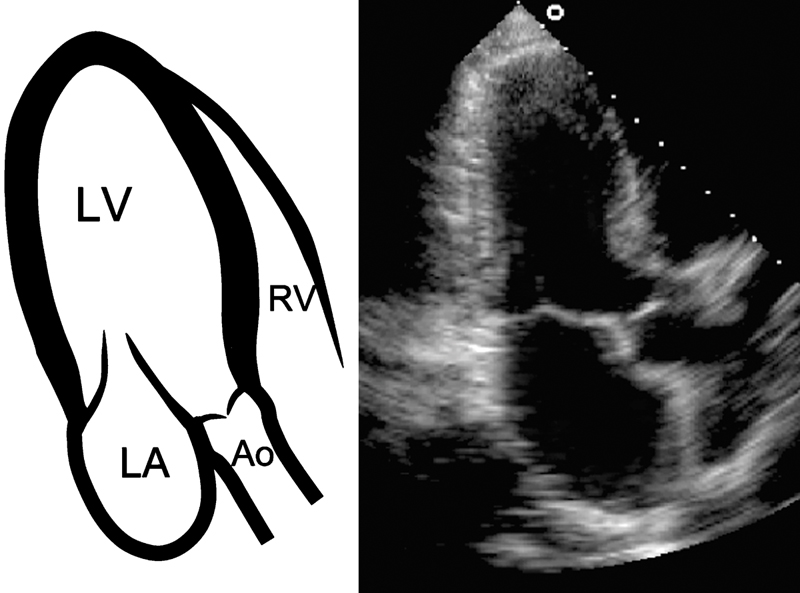

فحوصات تشخيصية لبعض امراض القلب والشرايين التاجية